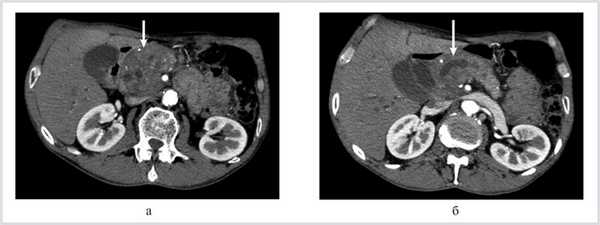

Больной Ш., 59 лет, оперирован 3 мес назад в одной из клиник города с подозрением на рак головки поджелудочной железы в объеме диагностической лапаротомии и пункционной биопсии. Гистологическое заключение: хронический панкреатит. После операции сформировался наружный панкреатический свищ. При поступлении больной предъявлял жалобы на постоянную боль в мезогастральной области, наличие жидкого стула и снижение массы тела. Установлен диагноз: хронический калькулезный панкреатит с изолированным поражением головки поджелудочной железы. Этот диагноз был подтвержден результатами мультиспиральной компьютерной томографии: имелись увеличение головки поджелудочной железы до 5—6 см (рис. 2, а), внутрипротоковая гипертензия в виде равномерной вирсунгэктазии (13—14 мм) без нарушения проходимости главного панкреатического протока (см. рис. 2, б).

Рис. 2. Компьютерные томограммы. а — увеличение головки поджелудочной железы (стрелка); б — расширение вирсунгова протока (стрелка).